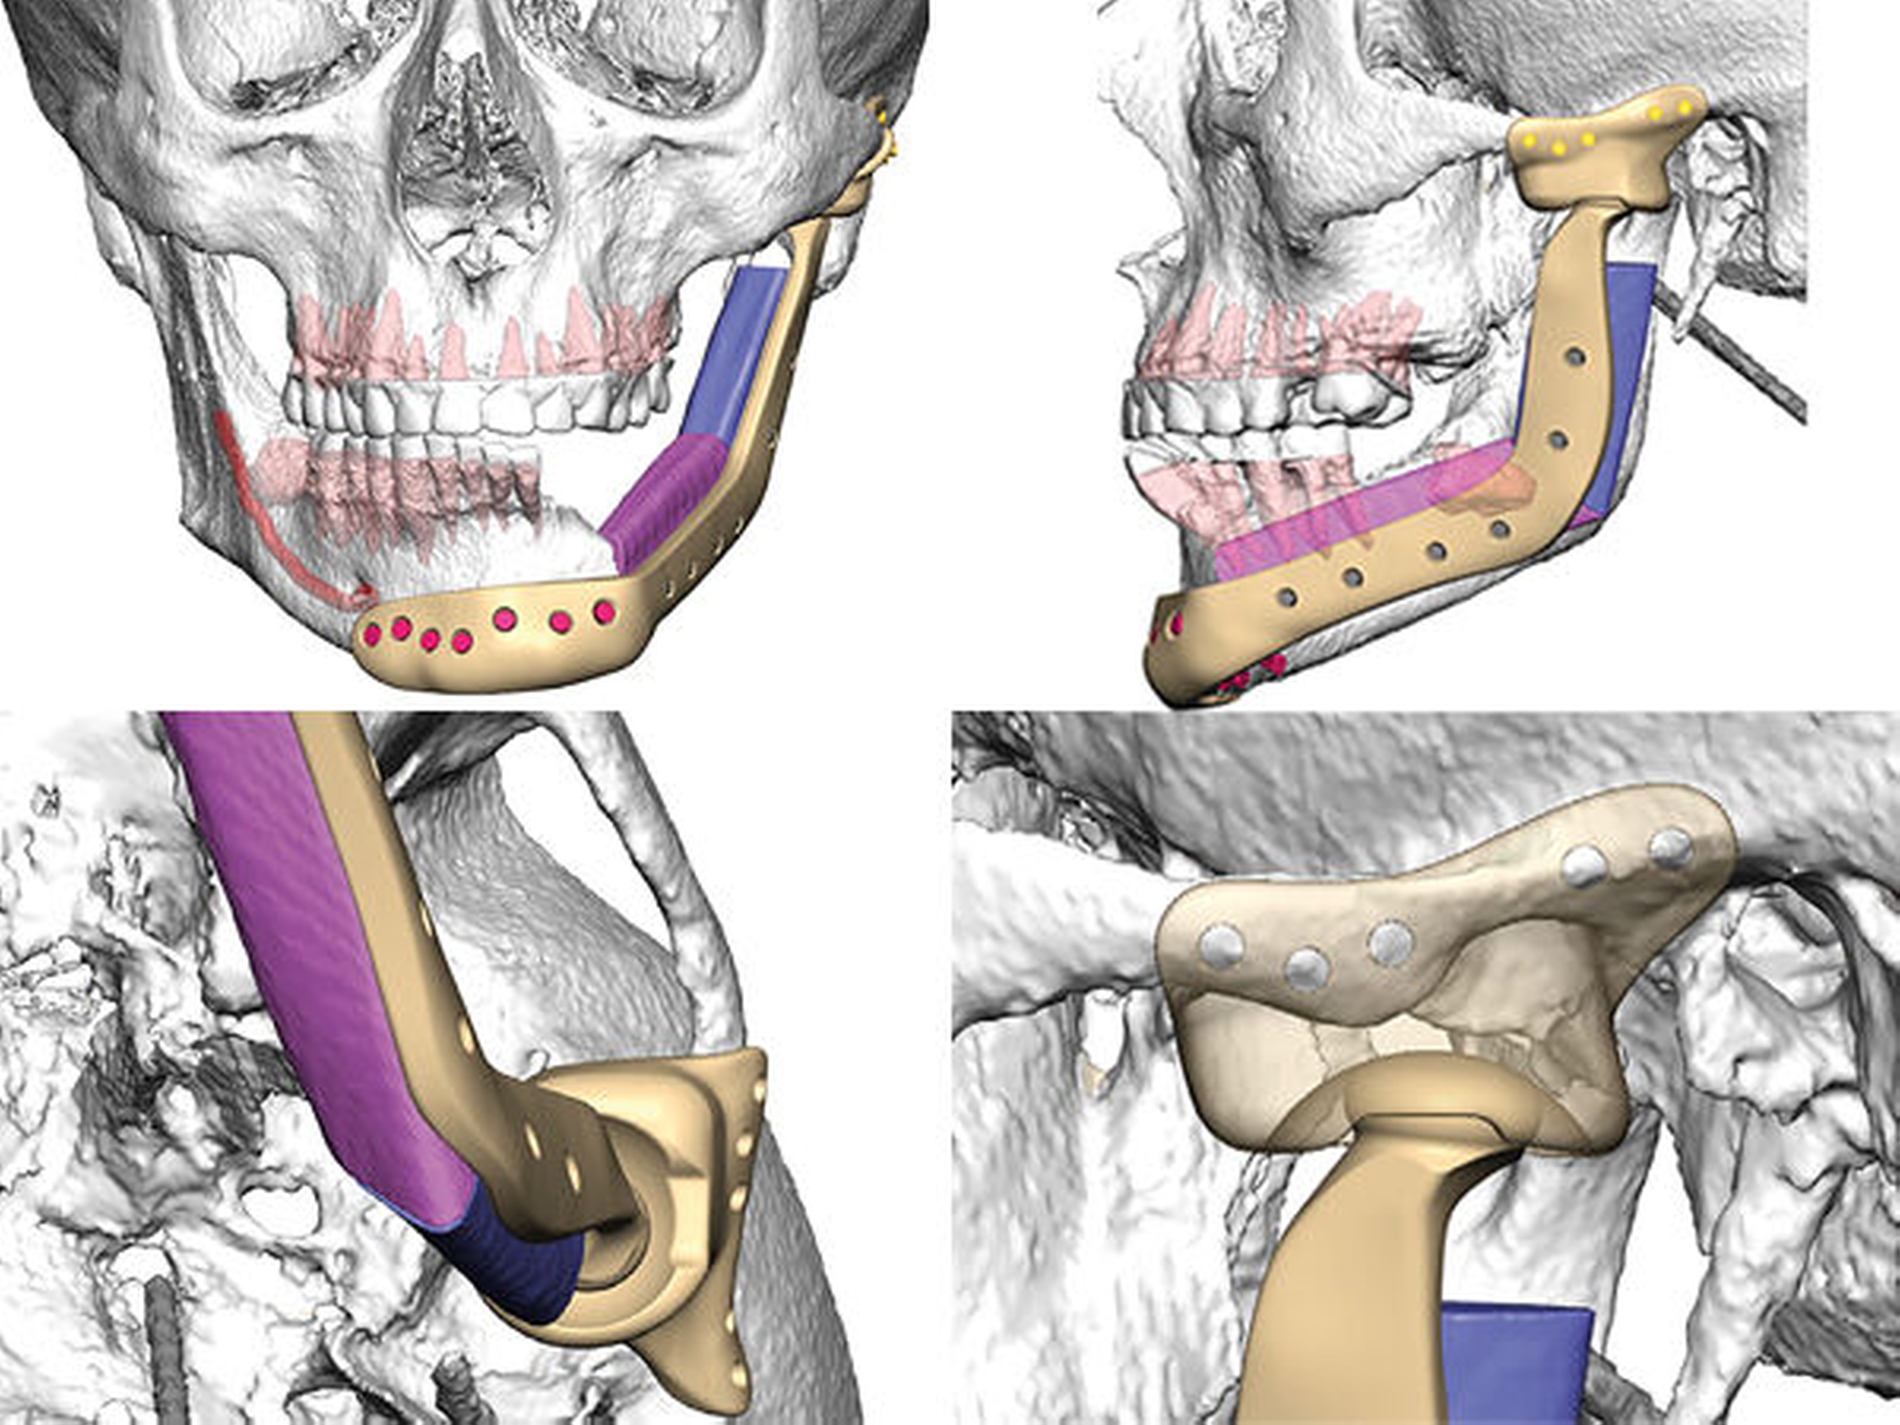

Die alloplastische Fossakomponente wird in der ehemaligen Fossa articularis platziert und am Arcus zygomaticus mit Schrauben fixiert. Bei dem BIOMET System wird der Rotationspunkt auf der Translationsbahn des natürlichen Kondylus nach kaudal gelegt, um die natürlichen translatorischen Bewegungen zu imitieren und die interinzisale Öffnung zu vergrößern [van Loon et al., 1999; van Loon et al., 2000]. In dem Plattendesign ist der Kondylus integriert, so dass hier keine Schwachstelle durch Schraubverbindungen entsteht (Abbildung 6).

Die zur Konstruktion der TEP konstruierten Teile, wie das PSI, die Fossa und Schablonen wurden durch Firma Biomet Microfix Inc. (Jacksonville, Florida, USA; [Vertrieb: Zimmer Biomet Deutschland GmbH]) hergestellt. Die Platte besteht aus einer Titan-Aluminium-Vanadium-Legierung, der Fossaanteil aus ultrahochmolekularem Polyethylen (UHMWE-PE) (Abbildung 7).

In Abbildung 8 sind die notwendigen Resektions- und Bohrschablonen dargestellt, die intraoperativ die Schnittgrenzen und Bohrlöcher festlegen.